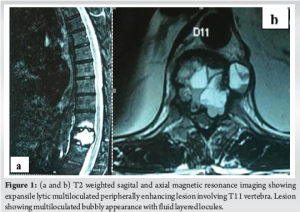

X-ray evaluation showed a pathological fracture of the T11 vertebra. Magnetic resonance imaging (MRI) dorsal spine showed expansile lytic multiloculated peripherally enhancing ill-defined lesion with a wide zone of transition replacing the entire normal marrow of the T11 vertebral body with grade II to thecal sac indentation, mild extramedullary thoracic cord compression with subtle cord edema. The lesion showed a multiloculated bubbly appearance with fluid-layered locules suggesting a possibility of ABC (Fig. 1). Differential diagnoses include Giant cell tumor, simple bone cyst, osteoblastoma, telangiectatic osteosarcoma, metastases, and plasmacytoma.

Case Report: A 68-year-old male presented to the outpatient department with complaints of left flank pain and abdominal pain for 4 months. Clinical examination showed tenderness in the thoracolumbar region with other spine examinations within normal limits. Magnetic resonance imaging dorsal spine showed an expansile lytic multiloculated lesion in the T11 vertebral body with mild extramedullary thoracic cord compression with subtle cord edema. The lesion showed a multiloculated bubbly appearance with fluid-layered locules. He underwent 2 stage procedure. In the first stage, posterior decompression, posterior stabilization, and biopsy were done. The histopathology report was consistent with ABCs. In the second stage, T11 corpectomy, tumor excision, and reconstruction with an expandable cage were done. Postoperatively his pain was reduced and was neurologically intact. At 4-year follow-up, clinically, he has excellent functional outcome and free of recurrence.